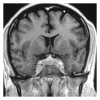

Inflammatory pseudotumor most commonly occurs in the orbit and produces orbital pseudotumor, but extension into brain parenchyma is uncommon. We report a case of inflammatory pseudotumor involving sphenoid sinus, cavernous sinus, superior orbital fissure, orbital muscle, and intracranial extension into left temporal lobe producing right hemiparesis and wernicke's aphasia. The patient improved clinically and radiologically with steroid administration. This paper provides an insight into the spectrum of involvement of inflammatory pseudotumor and the importance of early diagnosis of the benign condition.